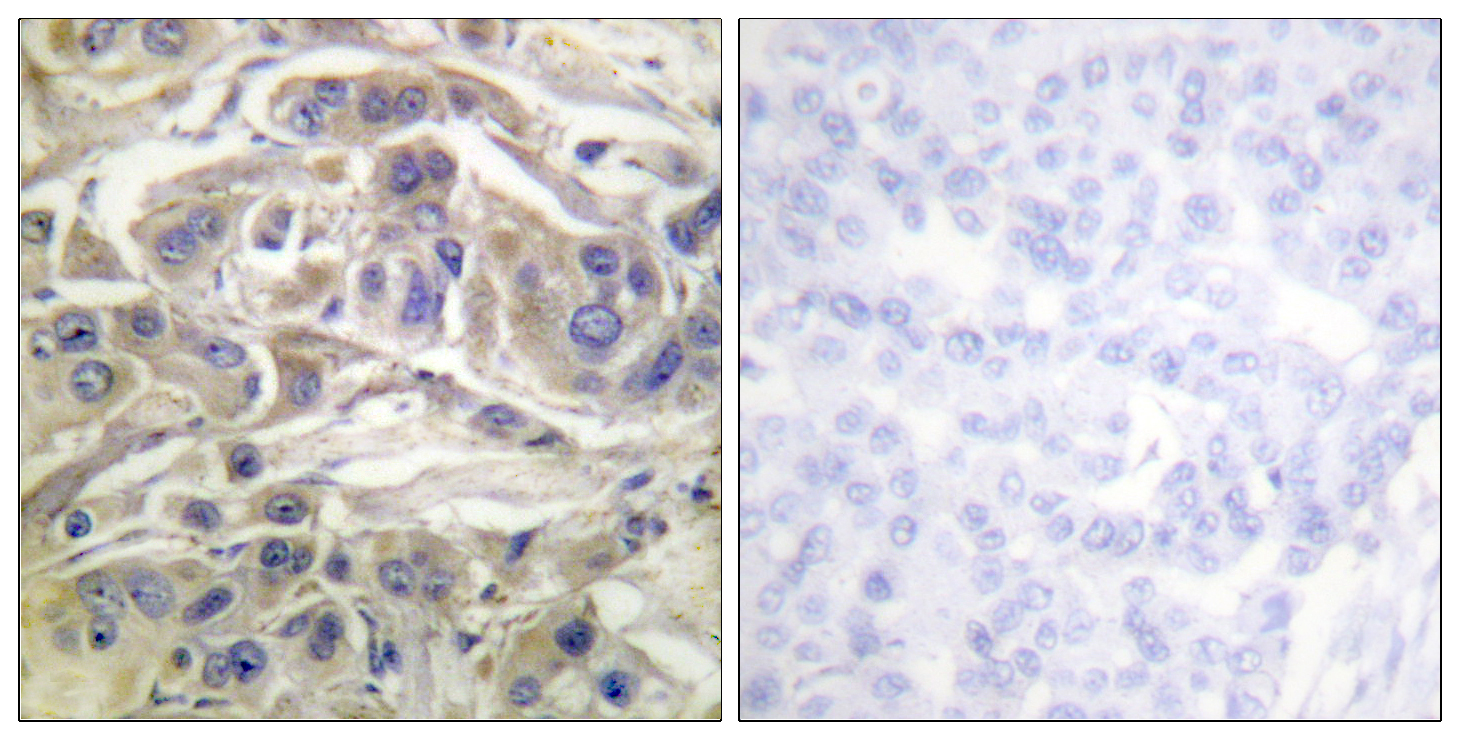

Anti-RapGEF1 AntibodyA99979

ApplicationsELISA, ImmunoHistoChemistry

ReactivityHuman